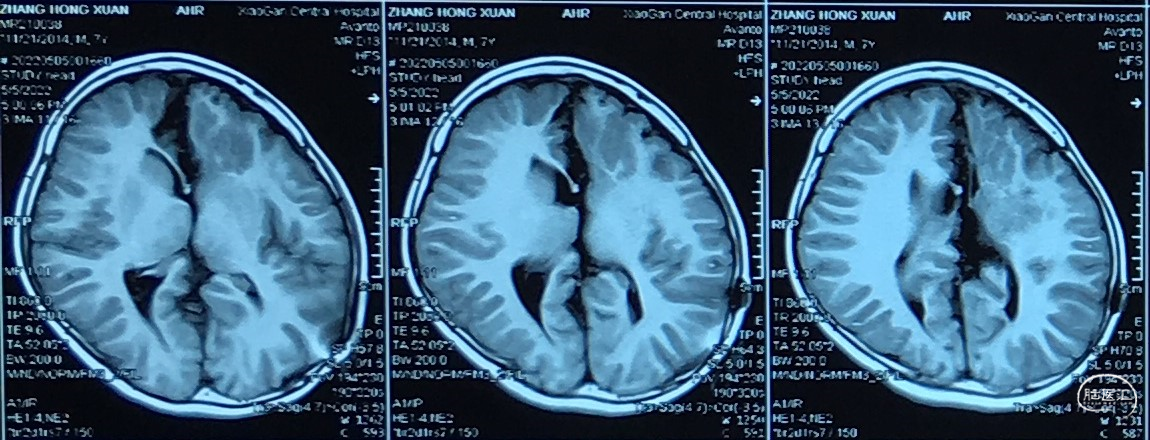

7岁 小学一年级,成绩较差、余无神经功能障碍

脑组织形态发育接近正常

但是,7岁某一天开始,间断头痛伴呕吐:

“颅内囊肿分流术后7年、间断剧烈头痛伴呕吐一月余”

诊断、处理???

1、分流管依赖(裂隙脑室)综合征。

2、病因:复张(发育)脑组织顺应性降低。

3、颅内压往往显著升高、间断剧烈头痛。

4、脑表面蛛网膜下腔间隙小、无法分流CSF。

术后7年,脑组织充分发育、形态接近正常。

出现分流管依赖、剧烈头痛(脑顺应性降低)。